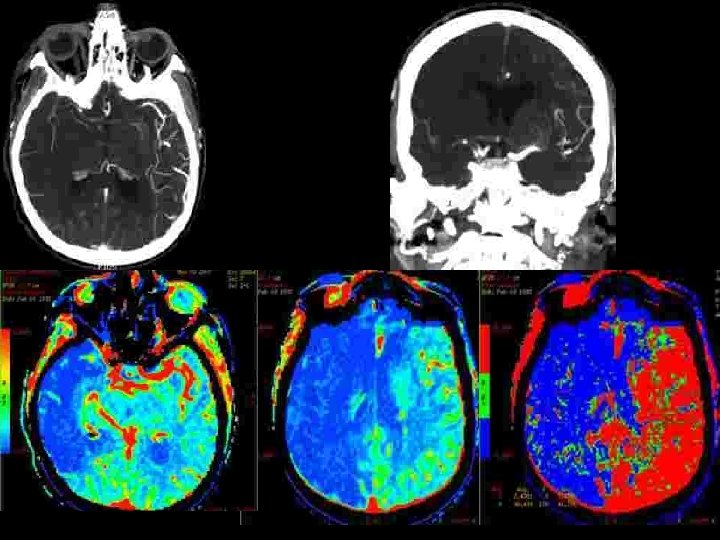

Occlusion en T de la carotide: pronostic effroyable • Evolution spontanée : – mortalité : 41 -50%, dépendance sévère : 29 -51% • Control group of the Duplex sonography in acute stroke study (27 patients avec traitement médical seul ) – Recanalisation (6 h) 1/27 – Hémorragies 6/27 (18%) – Évolution clinique (3 mois) • m. RS 0 -2 • m. RS 3 -5 • décès 0 17/27 (63%) 10/27 (37%) Wunderlich MT et al Cerebrovascular diseases 2005; 20: 355 -361

Occlusion en T de la carotide: pronostic effroyable • Pourquoi? • Deux facteurs principaux – Intéresse les artères lenticulostriées – Pauvreté de la circulation collatérale: l’artère communicante antérieure est elle perméable?

OCCLUSION du « T » CAROTIDIEN : RESULTATS DE LA THROMBOLYSE INTRA-ARTERIELLE CHEZ 21 PATIENTS • Etude rétrospective de 21 patients traités dans les 6 heures – – – 14 femmes, 7 hommes Age: 58. 4 ans (31 -84) NIHSS à l’admission: 18. 9 (12 -33) Délai de traitement: 262. 4 minutes (180 – 330) maladie cardio-embolique : 10 patients (47, 7%)

OCCLUSION du « T » CAROTIDIEN : RESULTATS DE LA THROMBOLYSE INTRA-ARTERIELLE CHEZ 21 PATIENTS • circulation collatérale – Artère communicante antérieure • Présente • Absente 14 7 – Opacification rétrograde de l’ACM • Jusqu’à la région insulaire • Incompléte • Absence 3 cas 9 cas • Technique • thrombolyse Mécanique • Mécanique +chimique 6 cas 15 cas * Urokinase (900. 000 UI): 7 cases * Actilyse (0, 9 mg/kg): 8 cases + 1/15 stenting carotidien cervical (sténose >90%)

Résultats Recanalisation • Immediate en Angiographie : – TIMI 0 6/21 – TIMI 1 5/21 – TIMI 2 -3 10/21 • DTC à 24 heures: Recanalisation - 13 cas (62%) Hémorragies 9 cas Transformation hémorragique 2/9 Hématome symptomatique 7/9 à 3 mois m. RS 1 m. RS 3 -4 décès 2/2 1/7 3/7

EVOLUTION CLINIQUE • A J 7 – – • A 3 mois (Modified Rankin Scale –m. RS) – – – • 7 morts (33, 3 %) (3 complications hémorragique) 14 patients survivants avec un score NIH de 6. 8 m. RS 0 -1 m. RS 2 m. RS 3 -4 10 patients 1 patient 3 patients résultats m. RS 0 -1 m. RS 2 m. RS 3 -4 m. RS 6 47. 7 % 14. 2 % 33. 3 % 4. 8 %

Conclusions • Le pronostic des occlusions en T de la carotide interne reste sévère – recanalisation (TIMI 2 and 3) moins fréquente que pour M 1 – complications hémorragiques plus fréquentes (7/21) • La thrombolyse intra artérielle améliore le pronostic • La thrombectomie mécanque améliore le taux de recanalisation et son délai